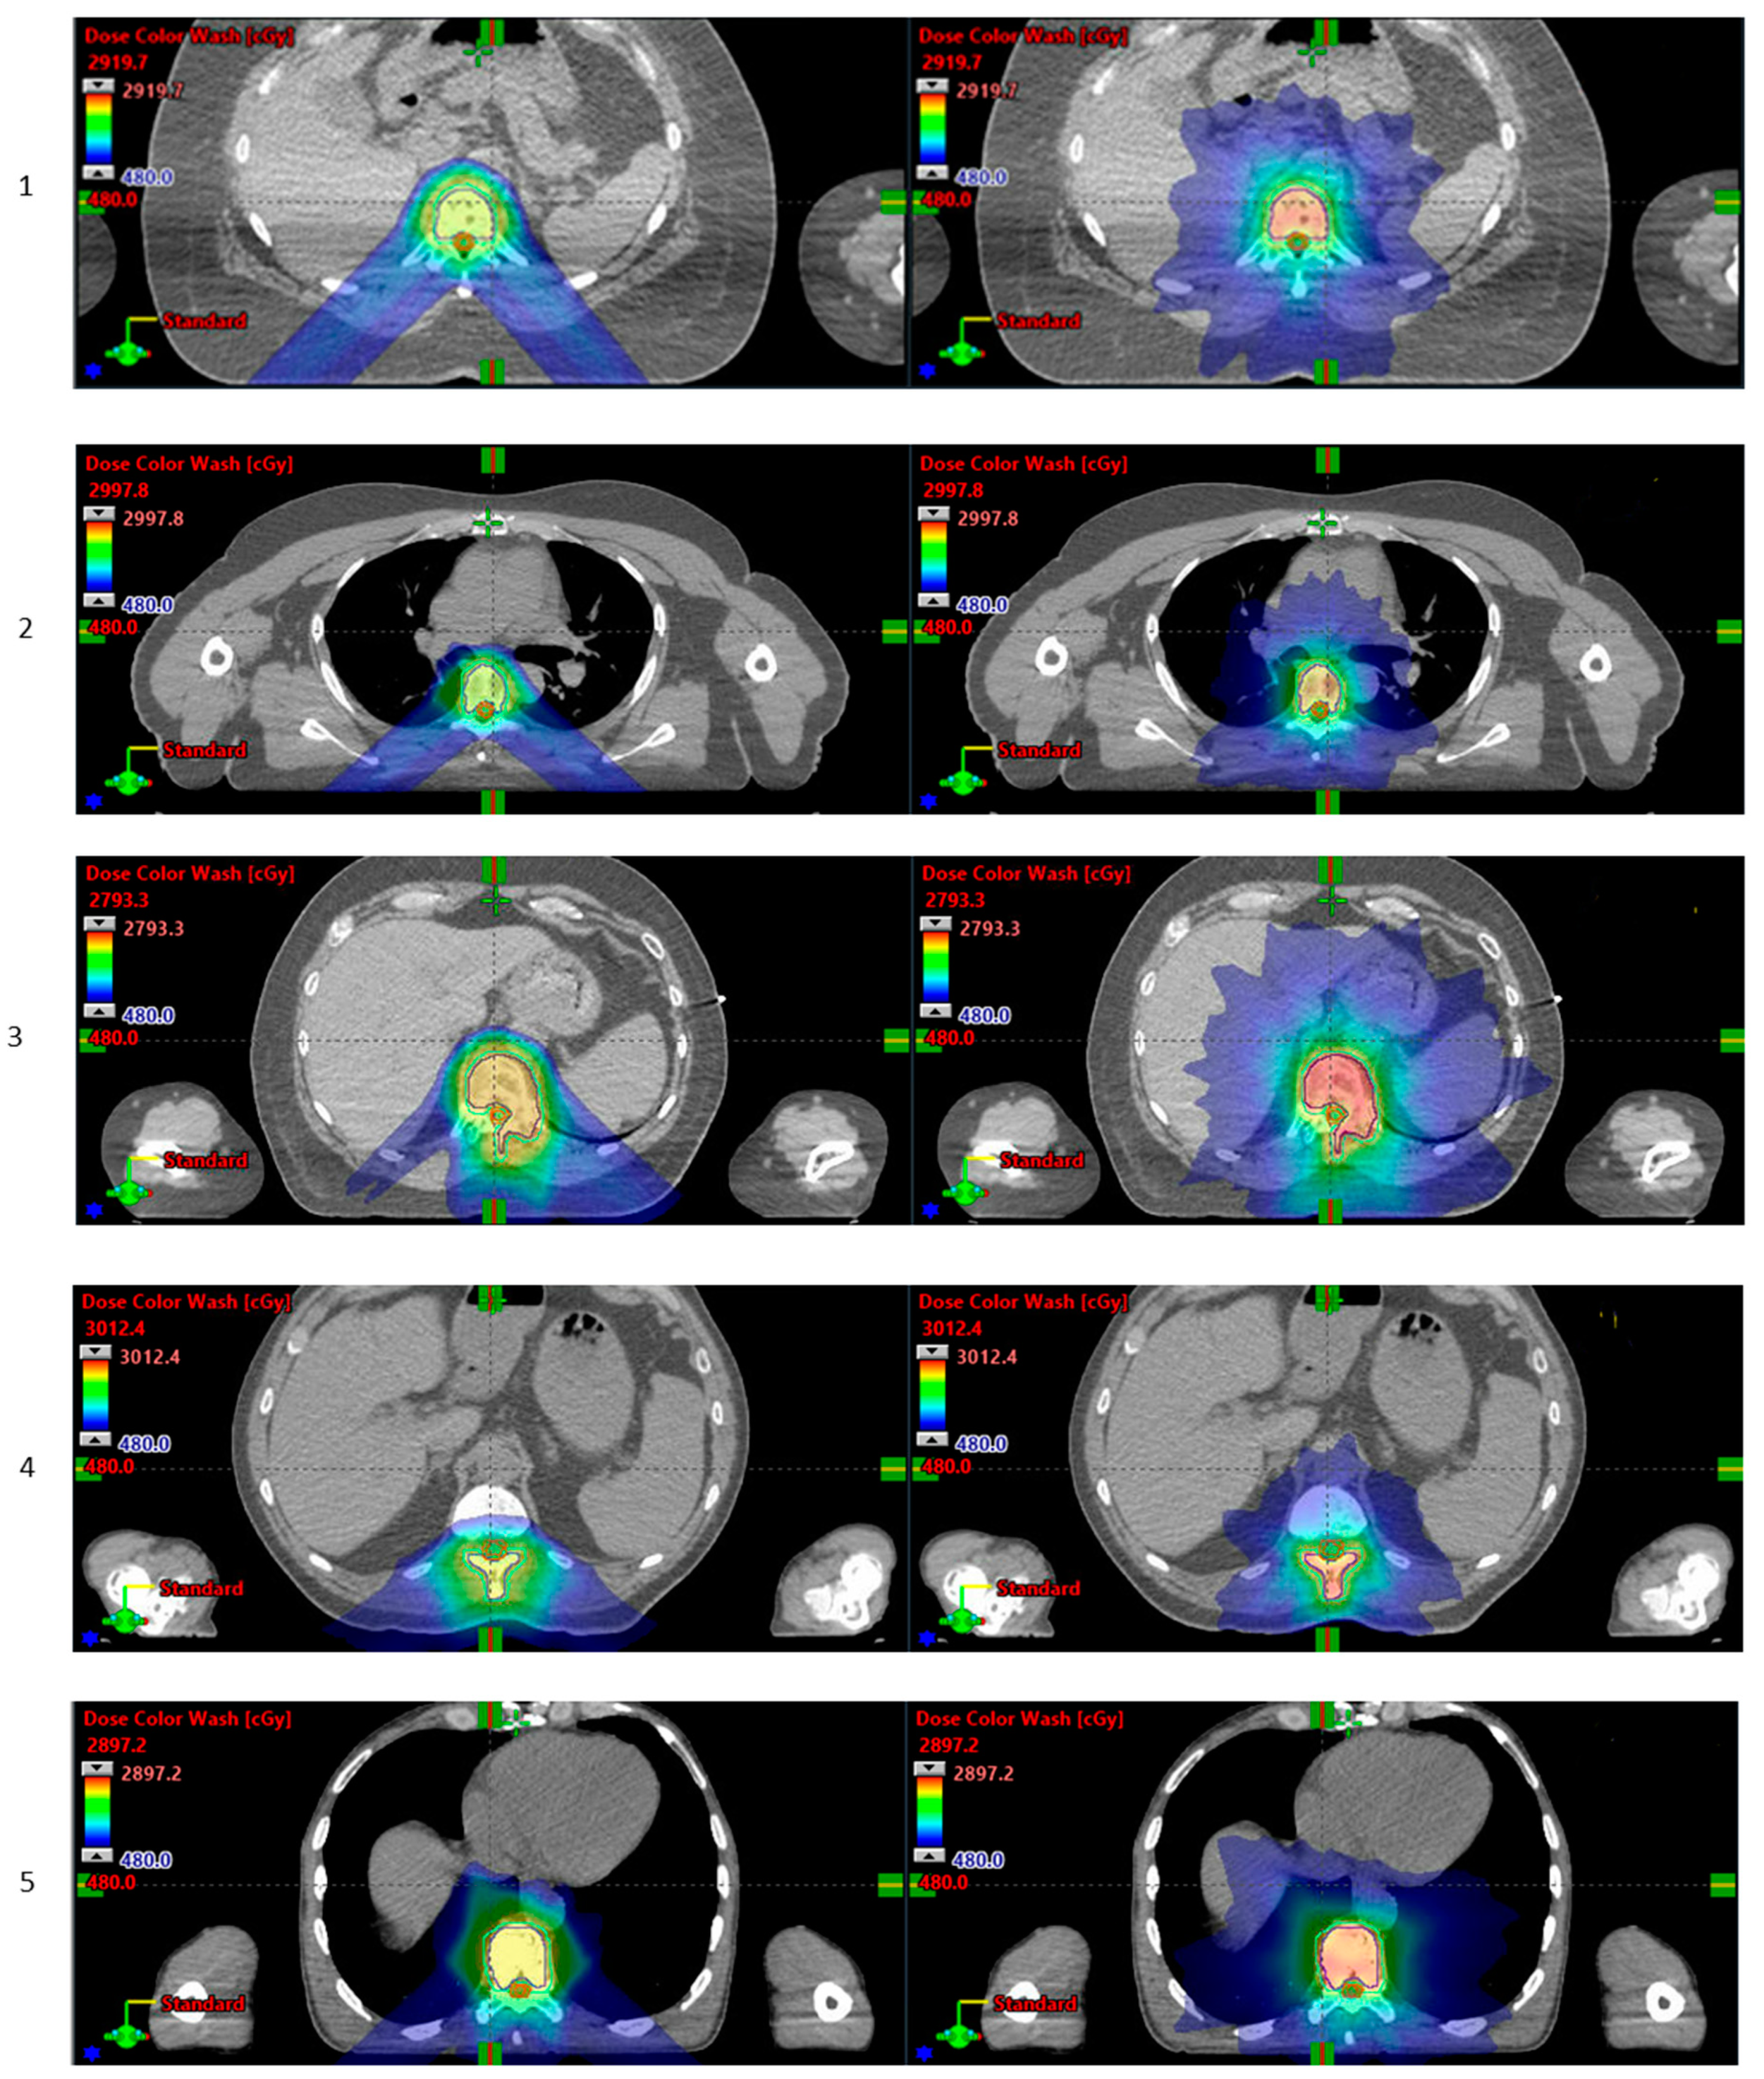

- Chuter, R.; Glassborow, E.; Speight, R.; Clarke, M.; Murray, L.; Radhakrishna, G.; Lavin, V.; Aspin, L.; Aldred, M.; Gregory, S.; et al. A treatment planning comparison of photon stereotactic ablative radiotherapy and proton beam therapy for the re-irradiation of pelvic cancer recurrence. Phys. Imaging Radiat. Oncol. 2022, 21, 78–83. [Google Scholar] [CrossRef]

- Rans, K.; De Meerleer, G.; Berghen, C.; Poels, K. Protons versus photons for oligometastatic prostate cancer: A planning comparison. Radiother. Oncol. 2022, 170, S1272. [Google Scholar] [CrossRef]